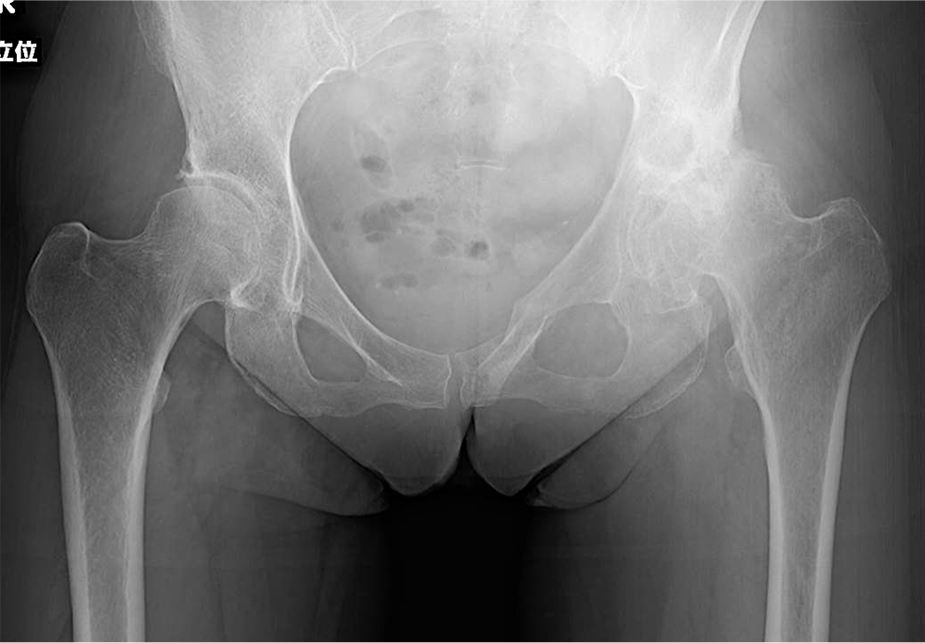

〈手術前のレントゲン〉

〈手術後のレントゲン〉(正面)